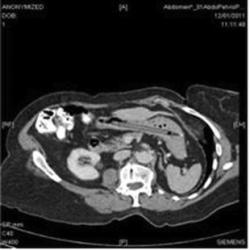

TRIBUNNEWS.COM - Seorang perempuan Inggris berusia 76 tahun baru-baru saja dioperasi untuk mengeluarkan pulpen yang tersimpan selama 25 tahun di dalam perutnya. Yang lebih mengejutkan, pulpen itu masih bisa berfungsi.

Dilansir Yahoo News, Rabu (21/12/2011), The British Medical Journal Case Reports menurunkan laporan tentang masalah kesehatan perempuan yang identitasnya dirahasiakan itu yang kasusnya dikirimkan ke ahli GI setelah mengalami sejumlah gejala termasuk kehilangan berat badan.

Saat dokter memeriksa perut wanita tersebut dan menemukan sesuatu di dalam perutnya. Setelah penemuan itu si perempuan baru ingat jika ia pernah menelan pulpen warna hitam sekitar seperempat abad silam.

Ketika pulpen itu dicoba ternyata masih mengandung tinta dan masih bisa digunakan untuk menulis. "Saat ia memeriksa ada apa dengan tonsilnya, pulpen yang dipakai untuk memeriksa masuk dan tertelan dengan secara tak sengaja. Dokter dan suaminya tidak percaya dengan cerita itu dan menganggap sakit perut yang dialaminya hanya normal saja. Dari hasil foto rontgen, tampak pulpen berada di bagian bawah perut tanpa ada luka apapun," demikian ujar Dr. Oliver Richard Waters.